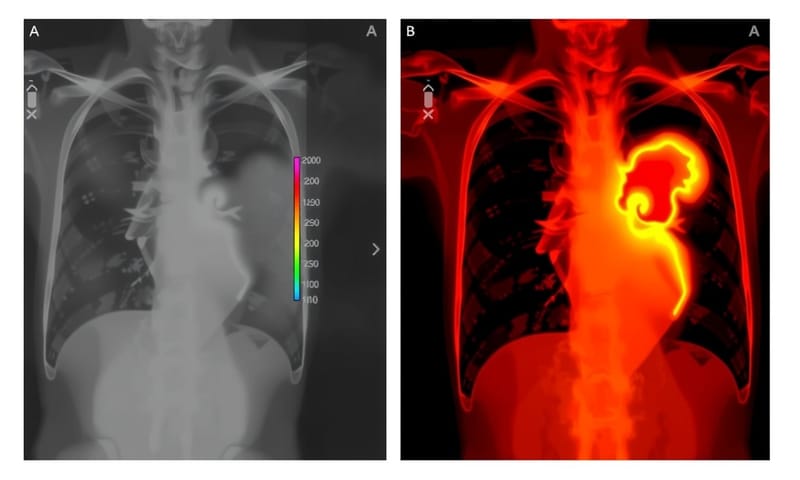

AIでがん検出、でも説明できなきゃ信じてもらえない壁

【💡 ソリューション】:うーん、イギリス拠点のチームがね、CNNベースの診断モデルを作ったんだって。なんか、そこにSHAPベースのエクスプレイナーを組み合わせてるらしいよ。まあ、正直言って途中で「それ、本当に役立つの?」とか思ったけど…でも実際には、X線画像やMRIのどこが診断結果に影響したかを可視化できる仕組みになってるみたい。それは意外とすごいかも。でも今ちょっとだけ別のこと考えてた、ごめんね。えっと、それで本題に戻ると、彼らはSHAP値をあらかじめオフラインで計算しておいて、その後FastAPI経由で必要な時に説明結果を返している、と聞いた。ちなみに使ったツールは `torch` とか `shap` 、それから `opencv` も挙げられていたし、もちろん `fastapi` もある。

【💥 ポイント】:医療分野では、「透明性」ってものが「精度」より重んじられることがある―ああ、本当なのかな?なんて時々疑問にもなるけど。でも事実として、モデル説明できないと倫理審査委員会から承認されない可能性が高いと思う。ま、いいか。